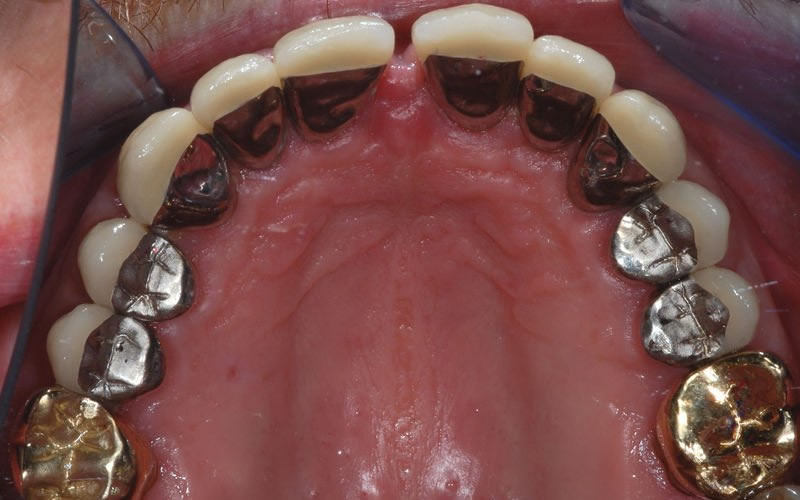

Case Studies

Dental Crowns (7 images)

Upper crowns and lower composites (4 images)